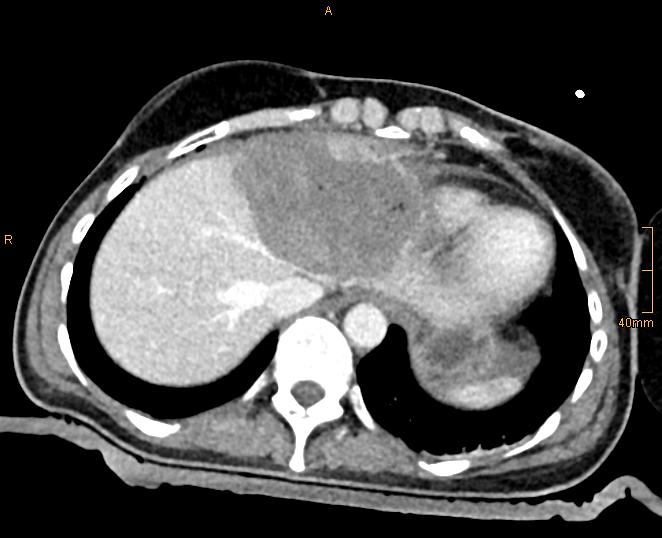

Figure 1C: Intraoperative contrast enhanced CT for verification of ablation result.

In 2001 we performed the first in man "stereotactic radiofrequency ablation (SRFA)" of a liver tumor 1 by introducing the stereotactic planning, image fusion and guidance principles into the field of thermal ablation. In contrast to the conventional "freehand" single-probe technique multiple probe positions are planned on 3D image datasets in order to cover the tumor by overlapping ablation zones. The whole procedure is performed under general anesthesia using muscle paralysis and respiratory triggering. An optical navigation system is used to adjust an aiming device for precise coaxial needle placement. Up to three radiofrequency electrodes are introduced through the coaxial needles for serial tumor ablation. Immediate fusion of the post ablation contrast-enhanced CT with the planning CT allows for rapid reliable intraoperative assessment of the result.

In the meantime, we have treated > 900 patients with > 3000 liver tumors in > 1500 sessions and collected them in our prospective SRFA registry. After bridging therapy with SRFA for liver transplantation, complete histopathological response was found in 183 of 188 treated lesions (97.3%) and in 50 of 52 lesions > 3cm (96.2%) 2. In a recent paper reporting the results after SRFA of very large tumors (> 8 cm) 3 (Figure 1) and in other studies including primary and secondary liver tumors the short- and long-term outcomes after SRFA were comparable to HR.